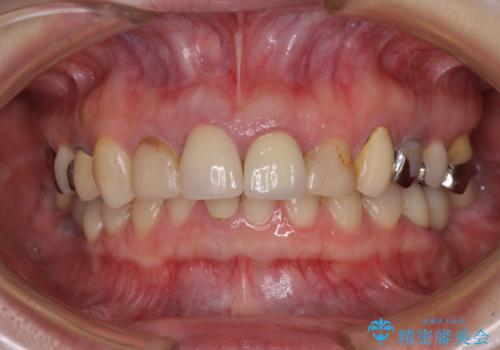

- 以前から前歯の根が折れていると言われていたものの放置しており、いよいよ痛みが気になってきたとのことで来院された患者様です。

歯肉移植により歯肉ラインや歯の形態を整えることができ、ブリッジによる補綴としたことで舞えば全体の色調を整えることができました。